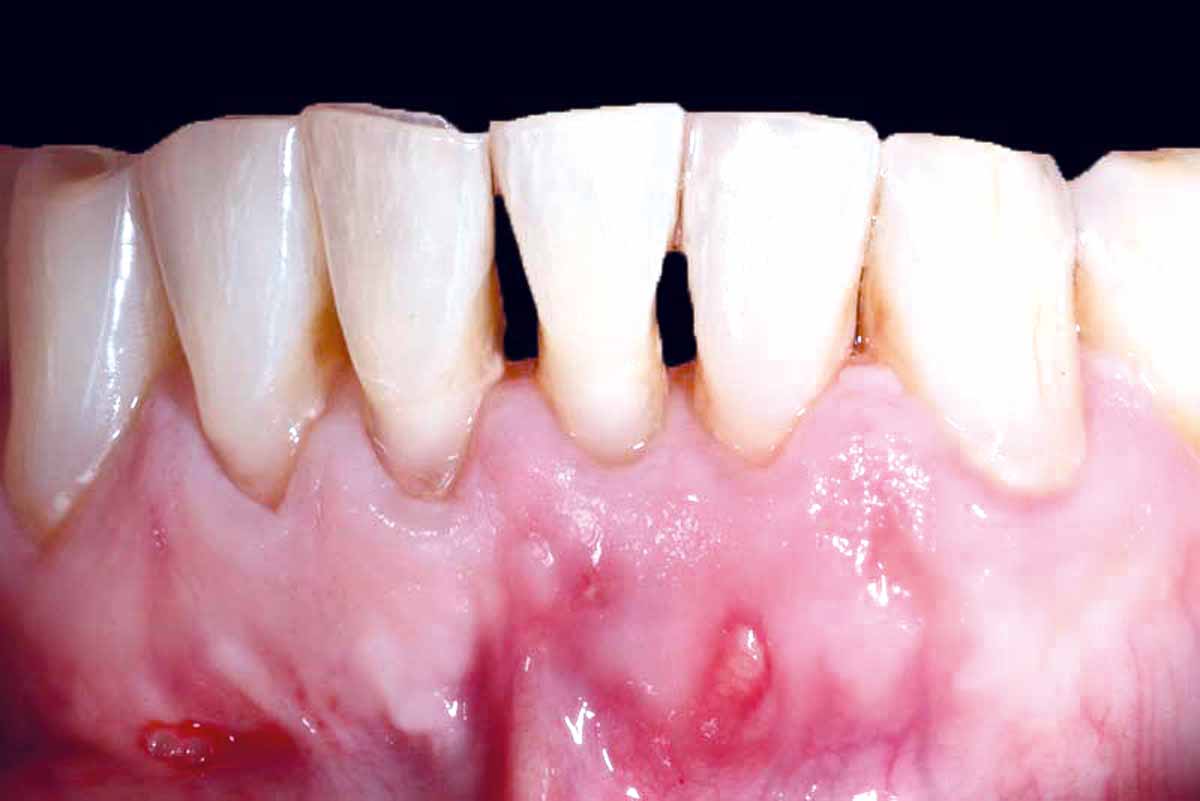

Pre-operative situation showing tooth 21 with deep periodontal pocket. Tooth presented with mobility grade III.